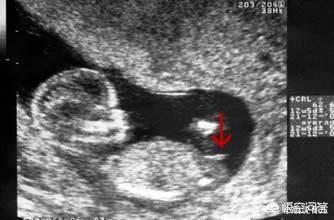

根据nt图可辨男女 摸清b超单这几个数据 胎儿就没啥小秘密了 快资讯

12周b超根据nub原理看男女 昨天发了一张b超图 之前不懂 宝宝树